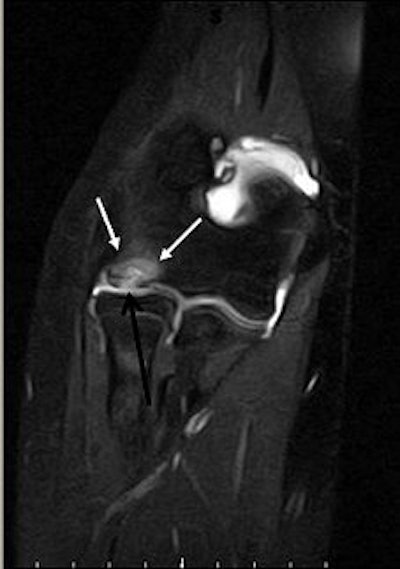

|  |

| Same patient as above. Top, sagittal T1-weighted MR image of elbow shows lesion (arrow) as large area of signal abnormality with low-signal-intensity rim and heterogeneous intermediate signal intensity and low signal intensity centrally. Below, sagittal fat-suppressed T2-weighted fast spin-echo MR image of elbow shows osteochondritis dissecans lesion (arrow) as large area of signal abnormality with high-signal-intensity rim and linear bands of high and low signal intensity centrally. Note marked irregularity of articular cartilage overlying osteochondritis dissecans lesion (arrowhead). |

| Kijowski R and De Smet AA, "MRI Findings of Osteochondritis Dissecans of the Capitellum with Surgical Correlation" (AJR 2005; 185:1453-1459). |